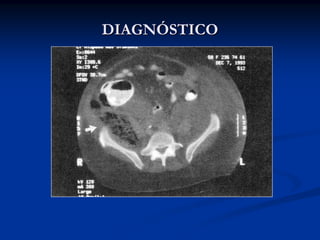

Achados a TC (contraste oral e venoso):

-   Ar adjacente ao duodeno, retroperitôneo

-   Fluido no retroperitôneo

-   Extravasamento de contraste no retroperitôneo

-   Edema da parede duodenal

-   Transecção do tecido pancreático

Mahesh V, CT of the Duodenum: An Overlooked SegmentGets Its Due. RadioGraphics 2001